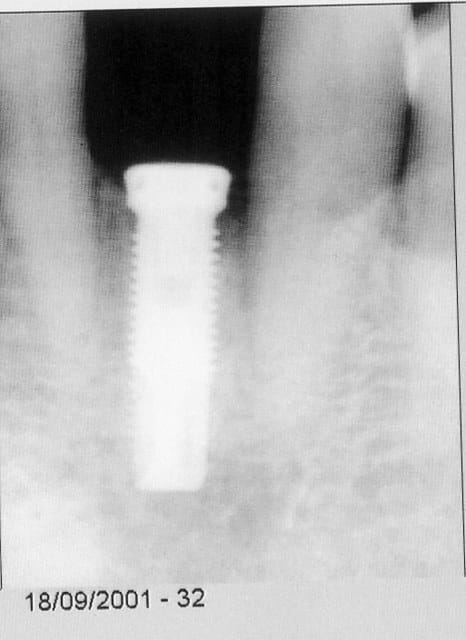

alors c'est un cas d'implant dans une bouche dégueulasse??? mais mon pauvre con, tu ne sais pas ce qu'est un implant, et tu ne sais même pas ce qu'est un patient visiblement. lorsqu'on remplace une dent par un implant, comme dans ce cas, pour des raisons parodontales, nous avons affaire à des gens porteurs d'une pathologie dont les causes ne disparaissent pas du jour au lendemain, ça c'est la dentisterie de tout les jours, c'est un cas de tous les jours, et tu veux peut-être un coup de karcher juste avant pour que ça brille?? pour épater la galerie?? est-ce que tu sais simplement comment réagit un implant dans un contexte parodontal?? regarde bien la radio de l'implant le jour de sa pose, et regarde ensuite la radio 3 ans après, en sachant que la patiente ne s'est pas pliée aux éxigences de la maintenance, tu vois quoi, gros con? un implant explosé? perdu? ne me réponds pas, tu le fera quand tu auras fait ton premier cas d'implants.